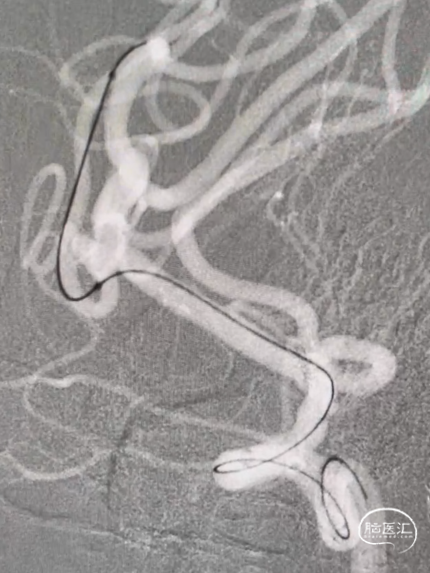

手术过程

Synchro14微导丝牵引支架微导管到位;弹簧圈微导管到位。

送入3*6mm弹簧圈成篮,同时摆一根支架微导管在上干,为T型支架做准备;

释放一枚Leo baby支架 2.5*25mm。

因下干支与M1成角太锐,支架在转弯处打开,多次推拉调整,以“神龙摆尾”方式释放,将支架尾端避开上干开口。

释放支架后,再依次送入2*3mm、1.5*2mm两枚弹簧圈完成治疗。

术后造影显示各分支血管通畅,动脉瘤不再显影。